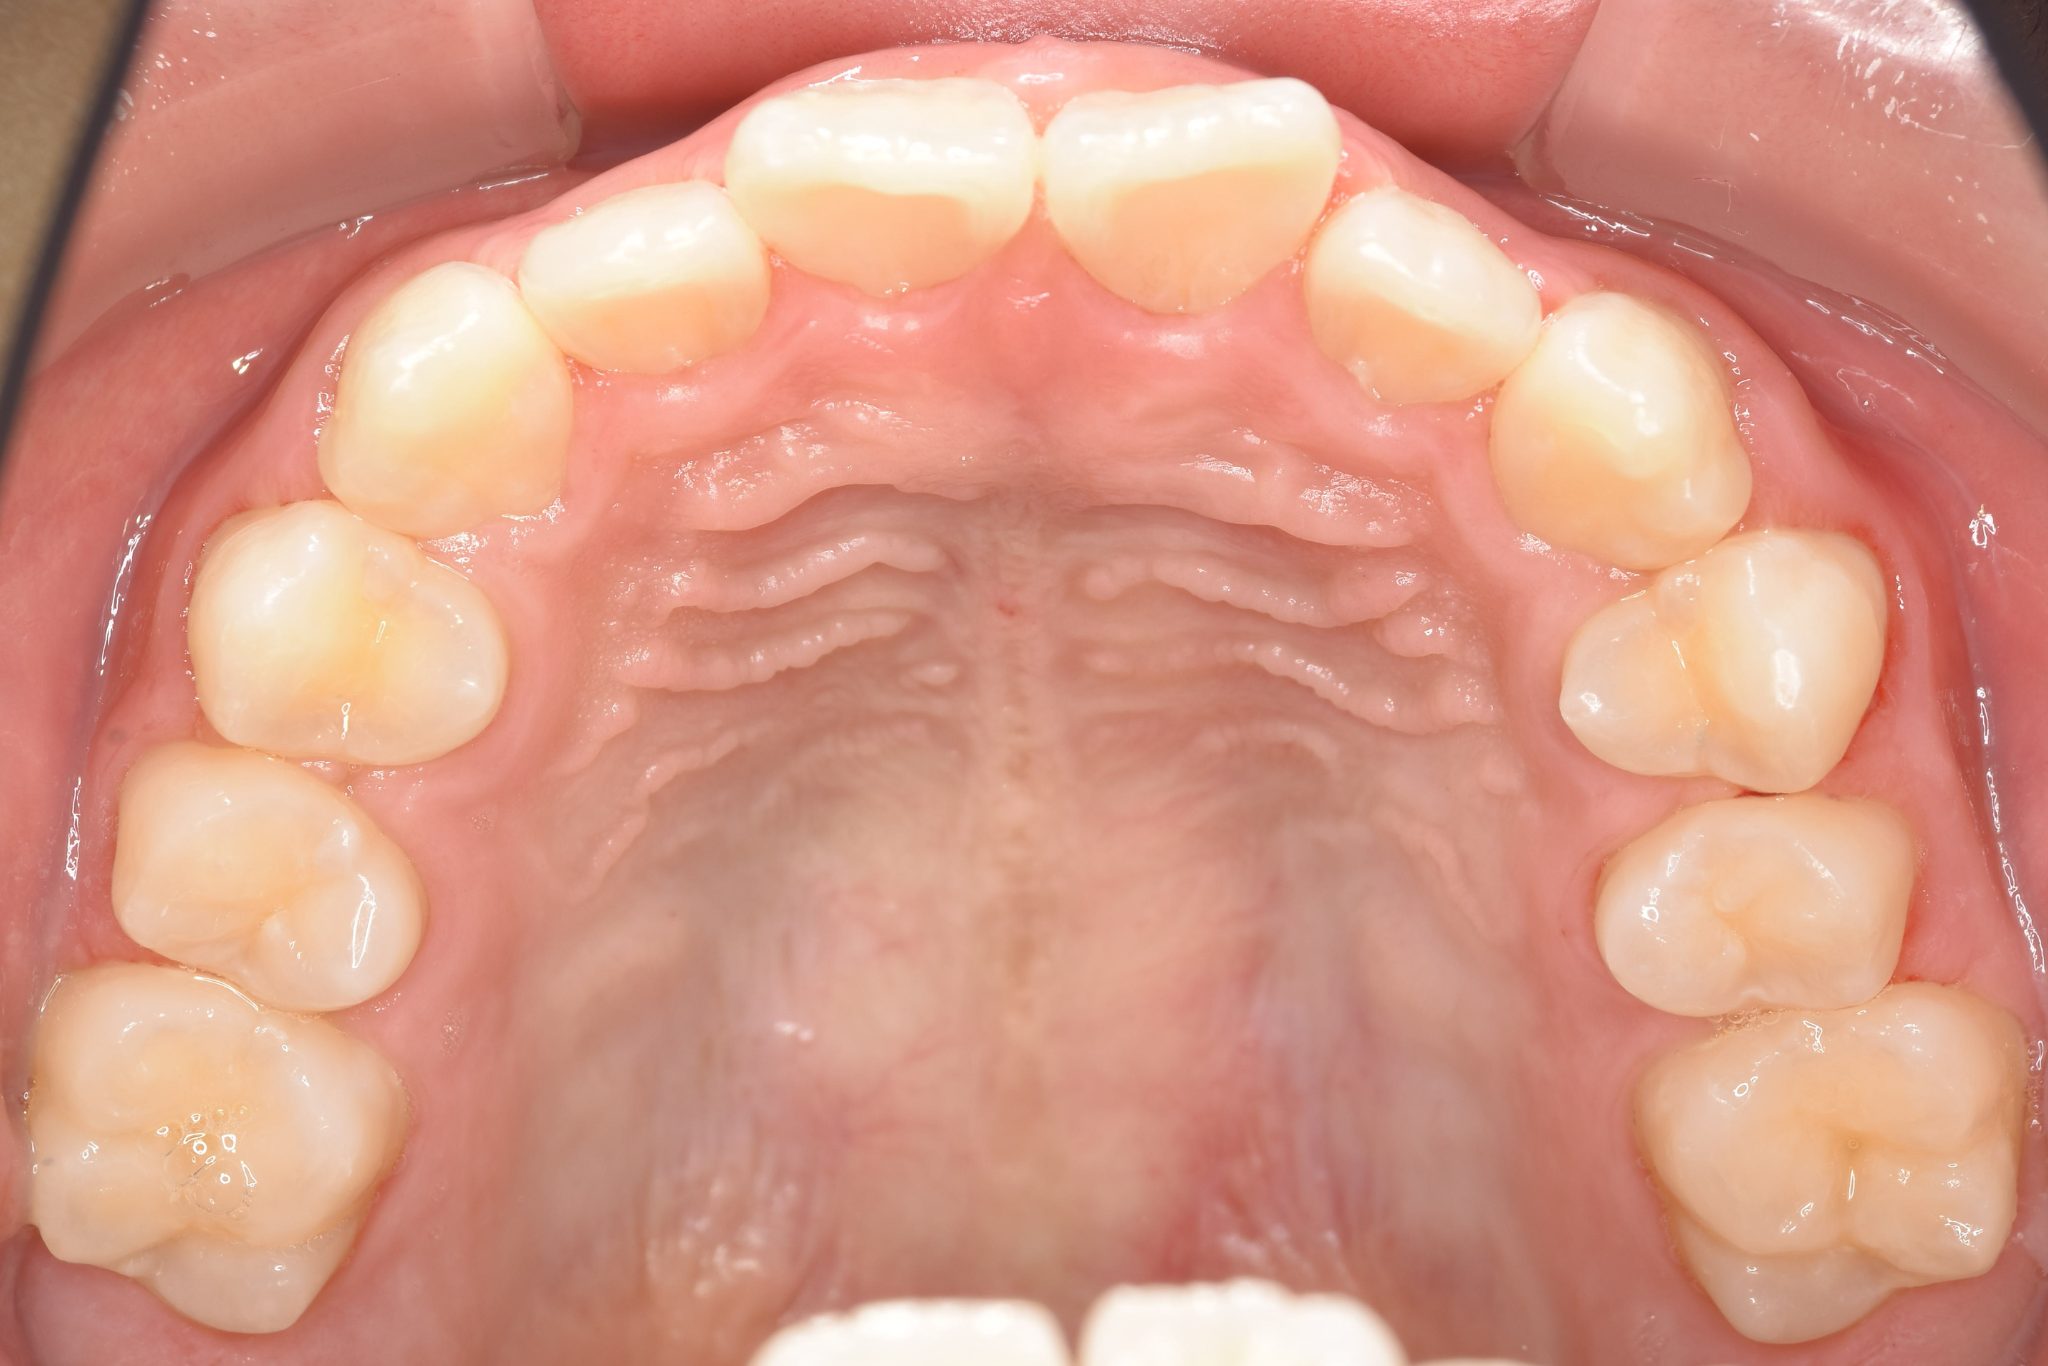

ビフォー

全顎ワイヤー矯正 症例_218

アフター

主訴 出っ歯|歯の隙間

施術内容 小児矯正1期治療

治癒期間 1年11ヶ月間

費用 465,400円(税込)